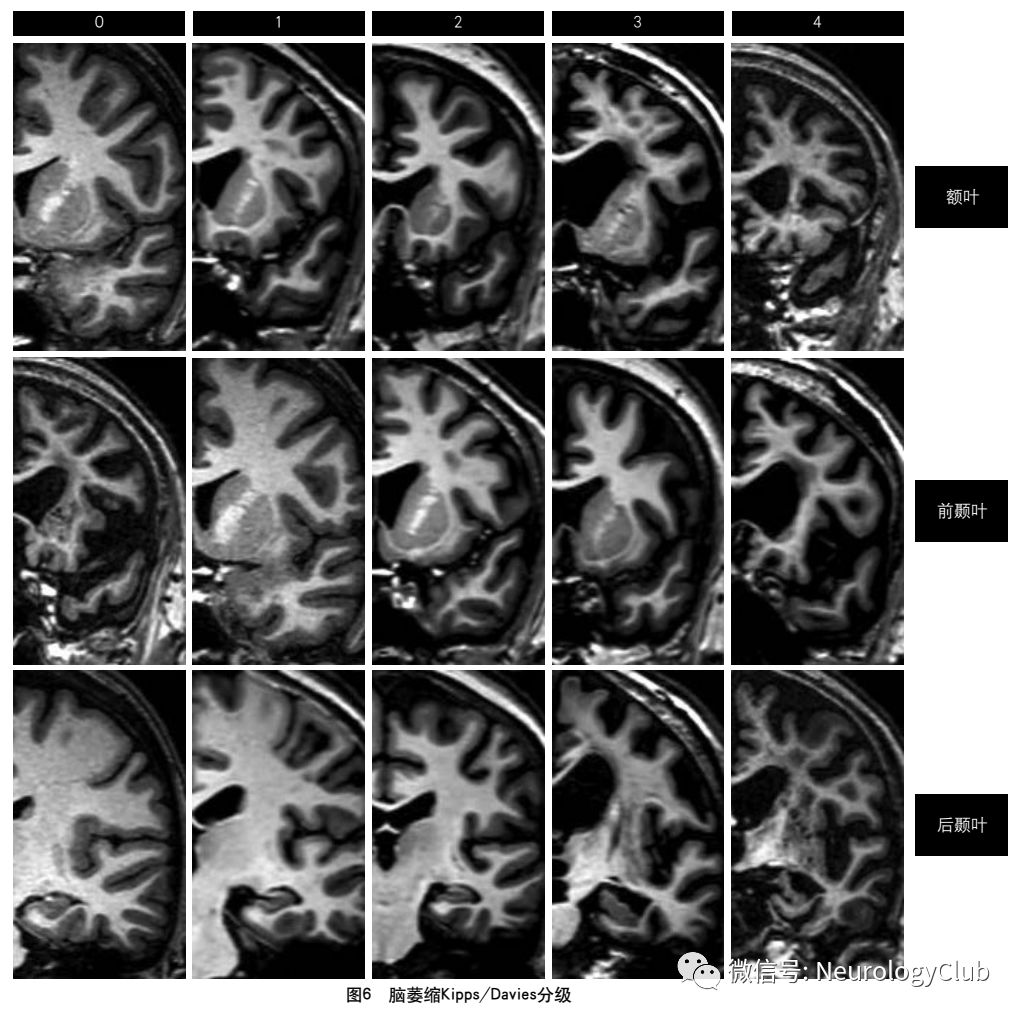

2013年的共识指南将脑萎缩定义为与特定的局灶性损伤,如脑外伤或脑梗死无关的脑容积减少脑萎缩可以是广泛的或局部的(如特定的脑叶或海马等特定区域),可以是对称或不对称的,亦可以是组织选择性的(如发生在白质等某一特定组织层)目前不同部位的脑萎缩有相应的诊断标准,全脑皮层萎缩分级用于评价全脑(图3);内侧颞叶萎缩分级主要评价颞叶内侧,重点是海马(图4);Koedam分级主要评价顶叶,尤其是扣带回和楔前叶(图5);Kipps/Davies分级主要评价额颞叶(图6)推测脑组织减少是由脑沟(周围)和脑室(中心)的脑脊液空间相对于颅内容积扩大所引起的